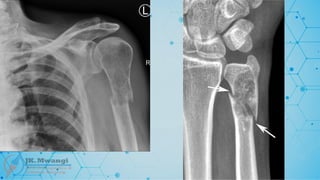

Colles fracture

 A fracture of the distal radius with dorsal (upward) displacement, often resulting

from a fall onto an outstretched hand. Named after Abraham Colles, who first

described the fracture in 1814.

Smiths fracture

 A distal radius fracture, but with volar (downward) displacement, often described

as the reverse of Colles' fracture. Named after Robert William Smith in 1847

Hutchinson's fracture (chauffeurs fracture)

 An intra-articular fracture of the radial styloid. Named after Jonathan

Hutchinson. It’s also called “Chauffeur’s fracture” because it commonly occurred

in early chauffeurs when hand-cranking a car engine.